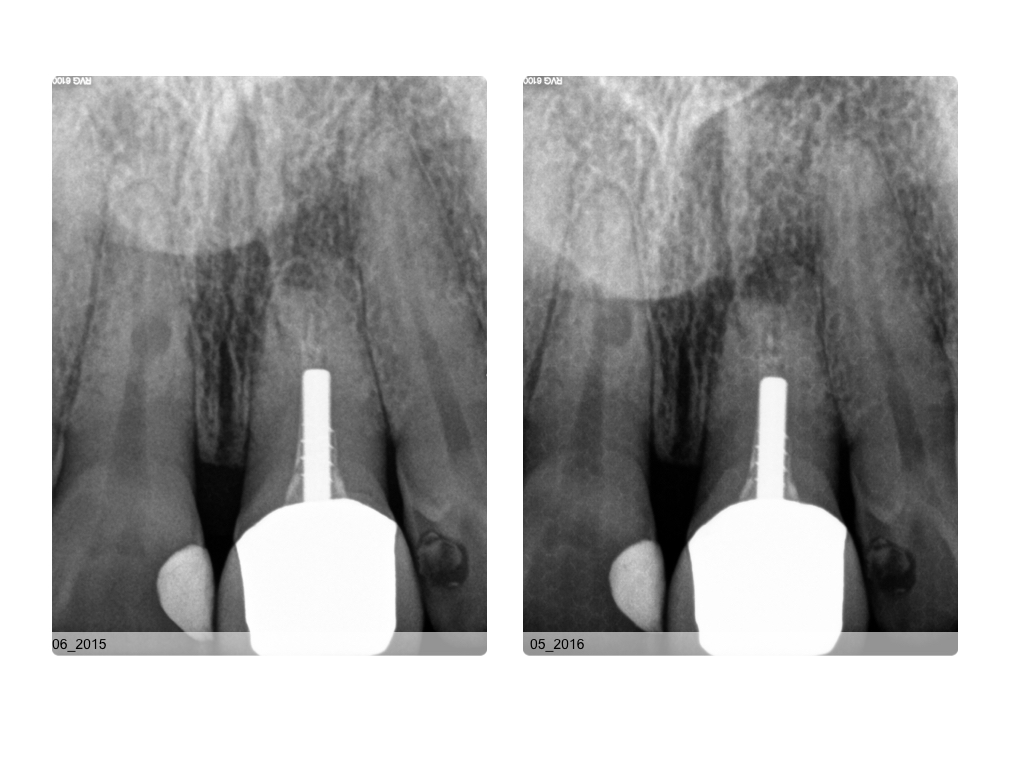

WS 04082016.004 Veröffentlicht 2. August 2016 am 1024 × 768 in Zustand nach traumatischer Zahnverletzung mit nachfolgender Wurzelbehandlung und Wurzelspitzenresektion